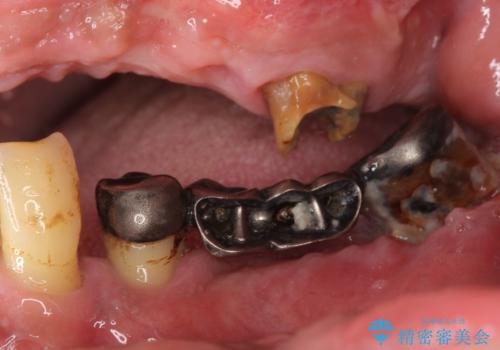

- 歯がないまま放置しており咬めないことを主訴に来院された患者様です。

仕事が忙しくなかなか自分のことに気が回らなかったそうですが、どんどん歯が抜け落ちて「もう限界だ!」と思い受診を決断したとのことでした。

精査したところ、全顎的な重度の歯周病により左上臼歯部は残根(左上6)を残してすべて欠損していました。

禁煙指導と歯周病治療後、左上臼歯部のソケットリフト(上顎洞底挙上術)及びインプラント治療(左上457埋入)を行いました。